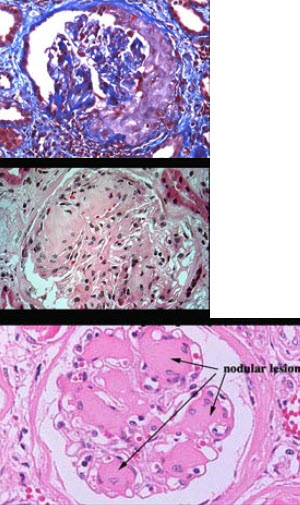

患者,女性,32岁,1型糖尿病15年,1年来间断眼睑及双下肢浮肿,血压160/90mmHg,尿蛋白(+),肾脏活检如图所示,尿糖(++)

E:糖尿病肾病